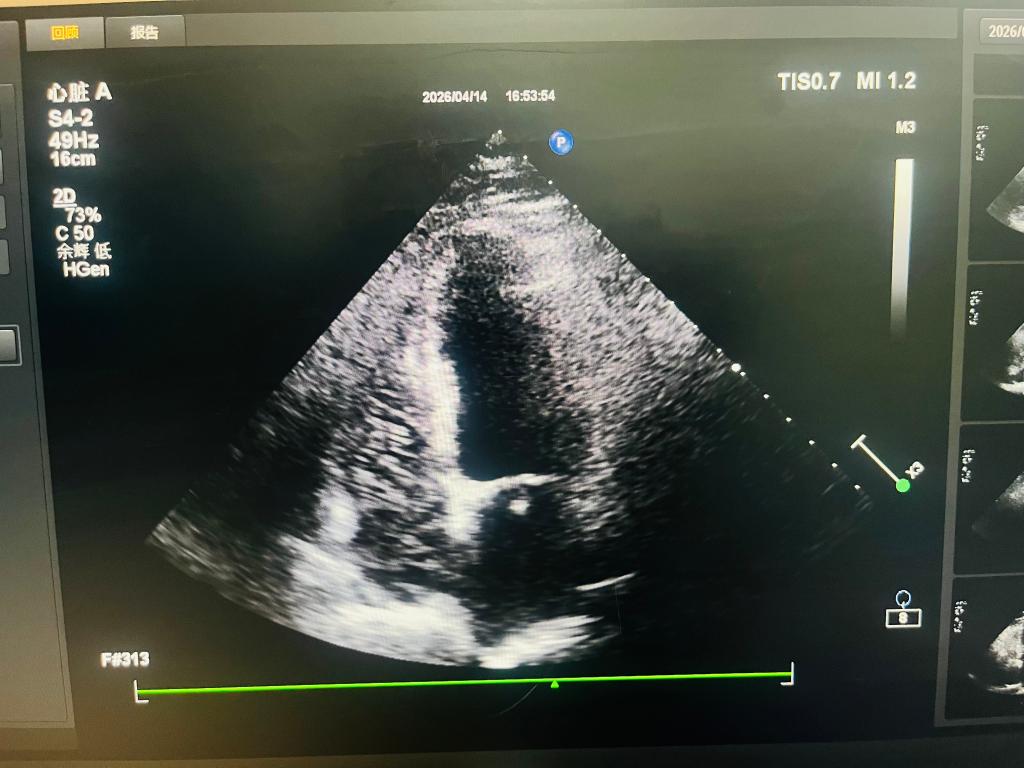

此次检查针对一名常规心脏超声提示房间隔搭错样改变、疑似过隔血流的患者。为明确病变性质、排除卵圆孔未闭,实施右心声学造影检查。检查过程中,功能科医师规范完成造影剂注入、动态显像观察、图像采集等全流程操作,细致捕捉心腔显影及分流征象,经严谨分析研判,最终确诊检查结果为阴性,排除卵圆孔未闭,为临床制定后续诊疗方案提供了客观可靠依据。